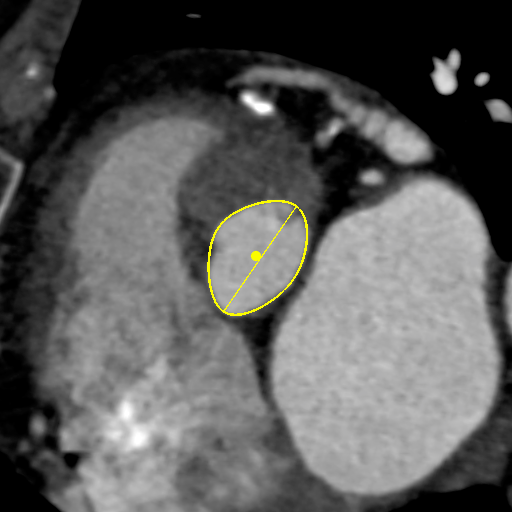

主动脉CT

主动脉瓣环平均直径:22.4mm

左室流出道平均直径:23.2

左冠脉开口:10mm

右冠脉开口高度:14.7mm

患者为功能性二叶瓣,左右瓣叶融合,左冠脉开口低,窦部大,冠脉风险低。

袁义强院长总结了该病例特点:功能性二叶瓣主动脉瓣狭窄,患者有心衰症状,解剖适合TAVR,年龄66岁,存在明确TAVR手术适应症。选择右股动脉入路,根据CT测量分析选择瓣膜大小,窦部情况可,瓣环平均直径22.4mm,选择植入24mm瓣膜。